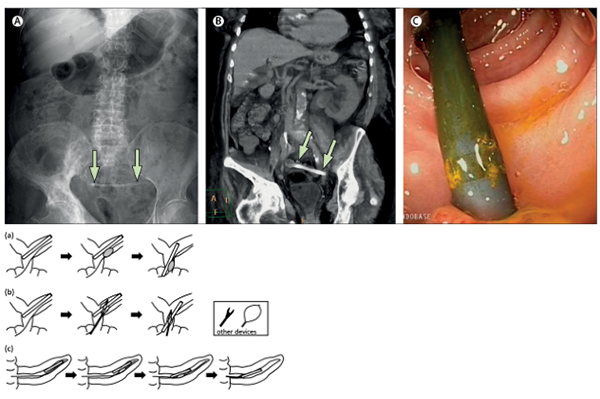

3.3 Stentolith: The End Stage

Unchecked encrustation transforms the stent into the core of a large pigment stoneâa stentolith. These complexes may reach several centimeters, fully encasing the stent and fixing it to the bile duct wall, rendering endoscopic extraction hazardous or impossible.

Proximal stent migration occurs in up to 10% of cases and is more common in benign strictures, dilated ducts, straight stents, and long indwelling durations. Migrated stents may lodge at the hepatic confluence, frequently embedded within stone or hyperplastic tissue.

Chronic exposure to bile acids and bacterial enzymes leads to polymer embrittlement. During attempted ERCP removal, the stent may fractureâoften at side holesâleaving proximal fragments without a retrieval handle.

When ERCP fails or is unsafe, LCBDE provides definitive single-stage management, often combined with cholecystectomy.

The transcystic route is usually impractical for intact retained stents due to their length and rigidity. A longitudinal choledochotomy allows controlled extraction and complete ductal inspection.